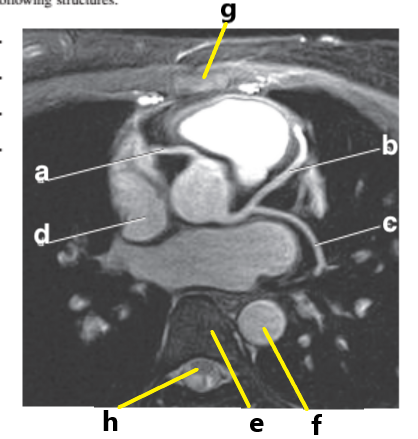

Which letter is the Pulmonary trunk ?

d

What is letter b ?

Left ventricle

Which letter is the superior vena cava ?

Left atrium

What is letter g ?

Right atrium

What is letter d ?

Pulmonary trunk

What is letter h ?